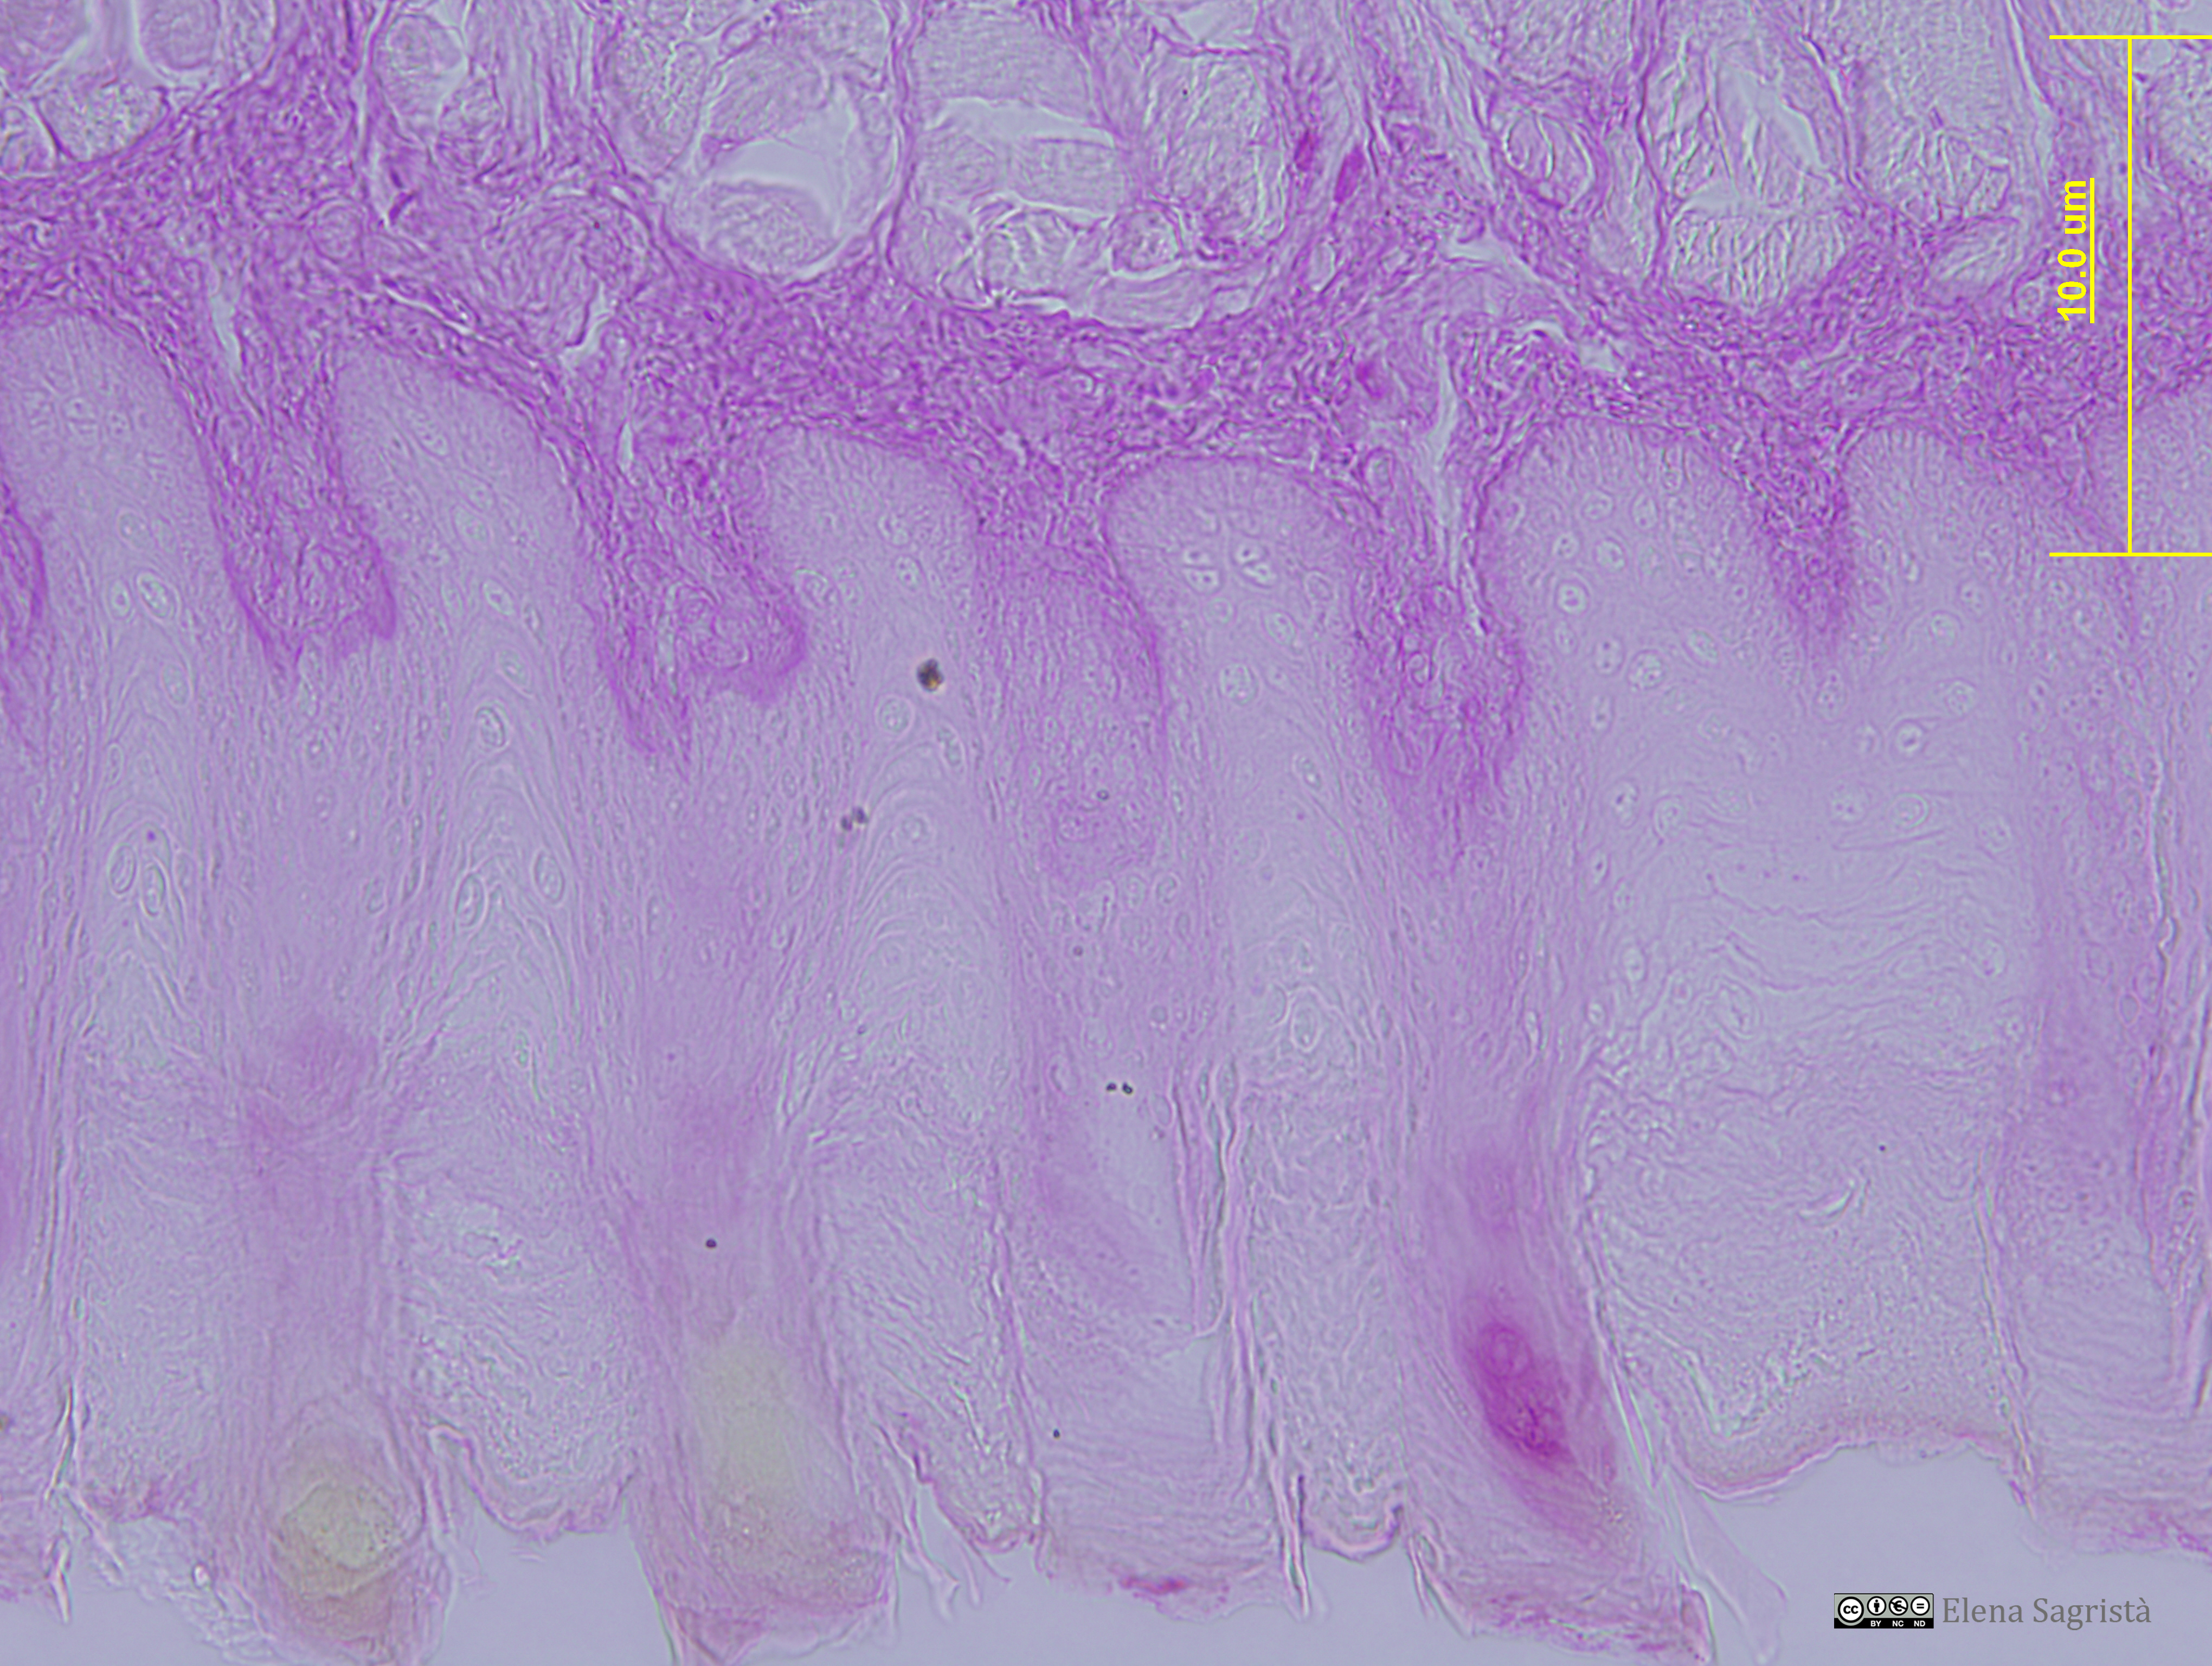

Imatges de preparacions histològiques de teixit epitelial. Microscopia òptica.